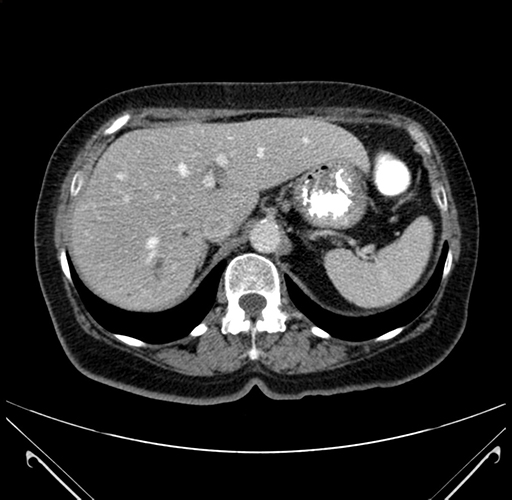

Pre-Chemo: Axial Venous

Pre-Chemo: Coronal Venous

Axial Venous

Coronal Venous

Imaging analysis

Based on your CT findings, which issue(s) would give reason for "planned slowing down moment(s)" in this case?

Considering a standard right hepatectomy procedure, what step(s) of the operation would you do differently in this case?